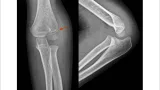

昨日大腿骨転子部骨折に対する手術を行った後期高齢患者さんの状態を確認するために, 9時に出勤.